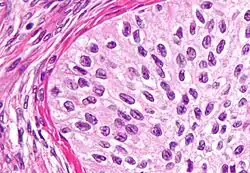

| High magnification micrograph of a Brenner tumor, a type of surface epithelial-stromal tumor. H&E stain. | |

Brenner tumor

Brenner tumors are uncommon surface-epithelial stromal cell tumors in which the epithelial cell (which defines these tumors) is a transitional cell. These are similar in appearance to bladder epithelia. The tumors may be very small to very large, and may be solid or cystic. Histologically, the tumor consists of nests of the aforementioned transitional cells within surrounding tissue that resembles normal ovary. Brenner tumors may be benign or malignant, depending on whether the tumor cells invade the surrounding tissue.